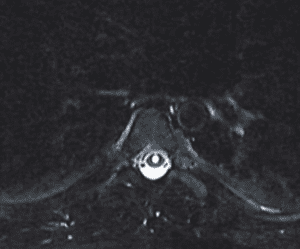

Fig 2. MRI of thoracic spine showing syringomyelia.